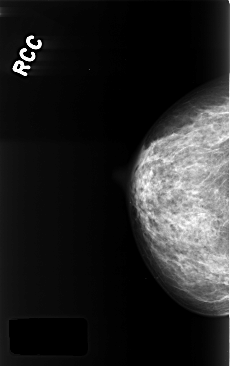

ics_version 1.0 filename C-0396-1 DATE_OF_STUDY 29 11 1996 PATIENT_AGE 68 FILM FILM_TYPE REGULAR DENSITY 3 DATE_DIGITIZED 13 10 1998 DIGITIZER LUMISYS LASER SEQUENCE LEFT_CC LINES 4376 PIXELS_PER_LINE 2864 BITS_PER_PIXEL 12 RESOLUTION 50 OVERLAY LEFT_MLO LINES 4376 PIXELS_PER_LINE 2808 BITS_PER_PIXEL 12 RESOLUTION 50 OVERLAY RIGHT_CC LINES 4392 PIXELS_PER_LINE 2760 BITS_PER_PIXEL 12 RESOLUTION 50 NON_OVERLAY RIGHT_MLO LINES 4392 PIXELS_PER_LINE 2808 BITS_PER_PIXEL 12 RESOLUTION 50 NON_OVERLAY |